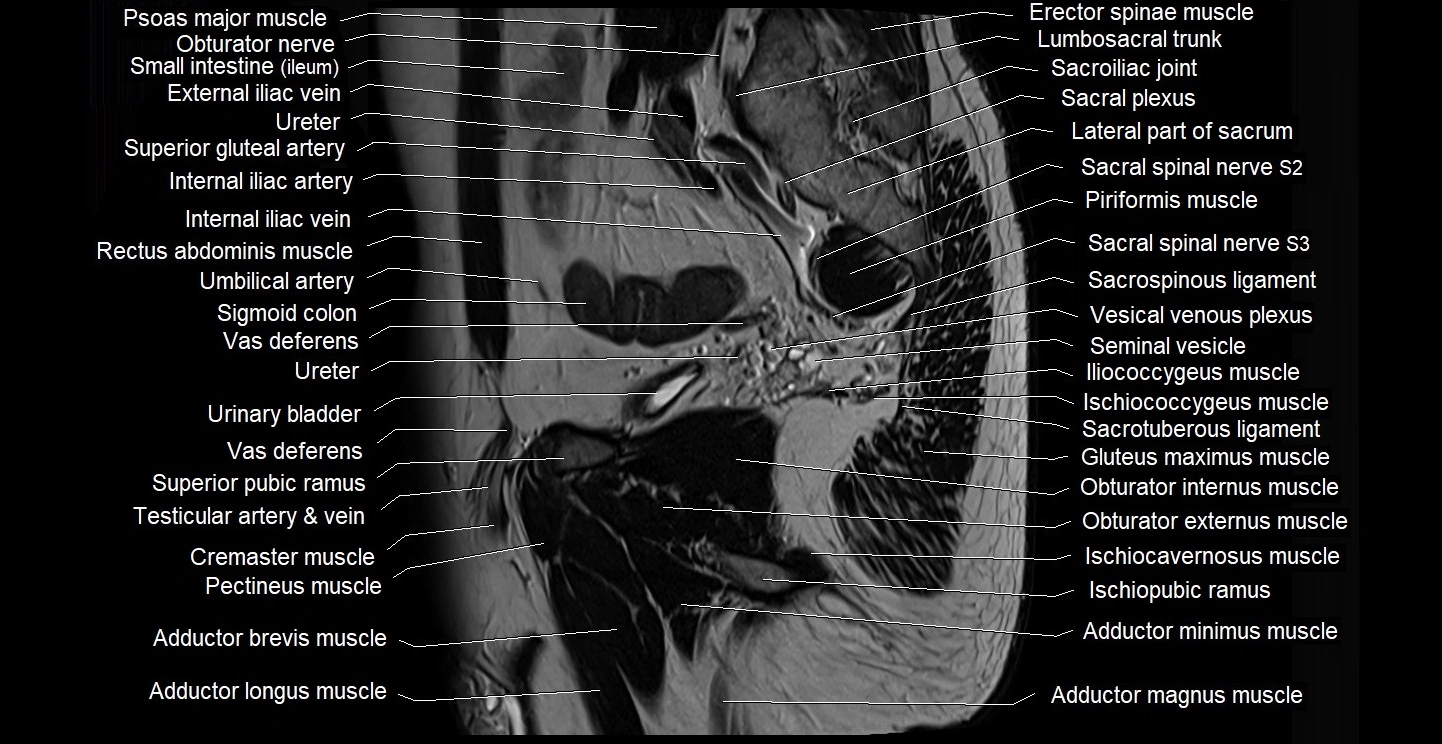

- Adductor brevis muscle

- Adductor longus muscle

- Adductor magnus muscle

- Adductor minimus muscle

- Cremaster muscle

- External iliac vein

- Internal iliac artery

- Internal iliac vein

- Lumbosacral trunk

- Obturator externus muscle

- Obturator nerve

- Pectineus muscle

- Piriformis muscle

- Psoas major muscle

- Sacral plexus

- Sacroiliac joint

- Sacrospinous ligament

- Sacrotuberous ligament

- Seminal vesicle

- Sigmoid colon

- Vas deferens